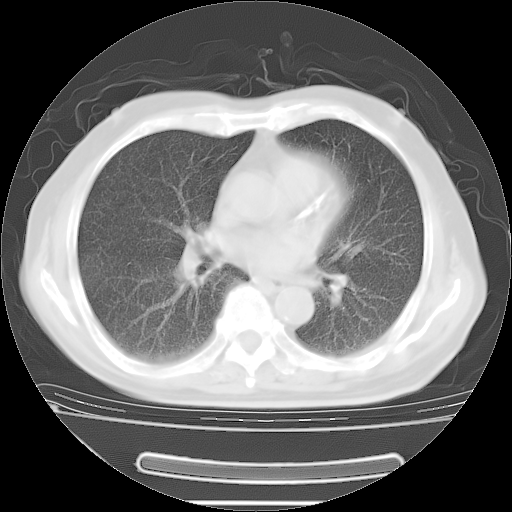

今天复查肺部CT,发现双肺广泛磨玻璃样改变。所以我把3月19日和5月9日相隔50天的肺部CT上传。请大家会诊。

2009年3月19日肺部CT片。

2009年3月19日肺部CT

大致读了系列胸部CT:纵隔窗无明显异常,肺窗:从4、27至今:主要是双肺中下野外带可见毛玻璃样改变,目前处于急性肺泡炎阶段,至于原因考虑1、结替组织或胶原血管性疾病所致?2、恶性疾病如恶组在肺部所致的表现或细支气管肺泡癌?3、药物或其它原因如肺蛋白沉着症所致肺泡炎目前不太可能?总之,明天就去请我院的呼吸科、感染科、血液科和临免专家会诊哈。